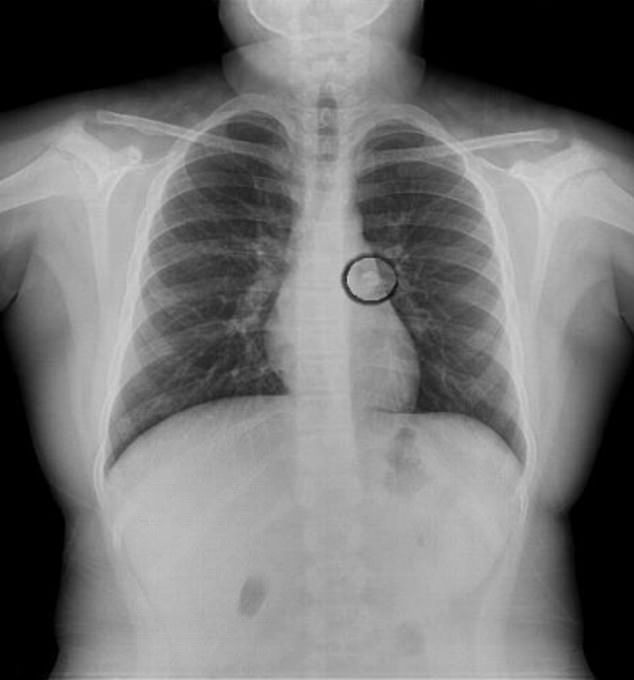

Podczas badań lekarz usłyszał szmer w lewym płucu dziewczynki. Zlecił wykonanie badania rentgenowskiego klatki piersiowej. Okazało się, że w oskrzelach tkwi ząb, który dziewczynka straciła w nocy. Podczas snu ząb przedostał się do jej dróg oddechowych. Wszyscy byli zaskoczeni tym widokiem.

Ząb utknął w oskrzelach dziewczynki

Ząb utknął w oskrzelach dziewczynki © dailymail.co.uk